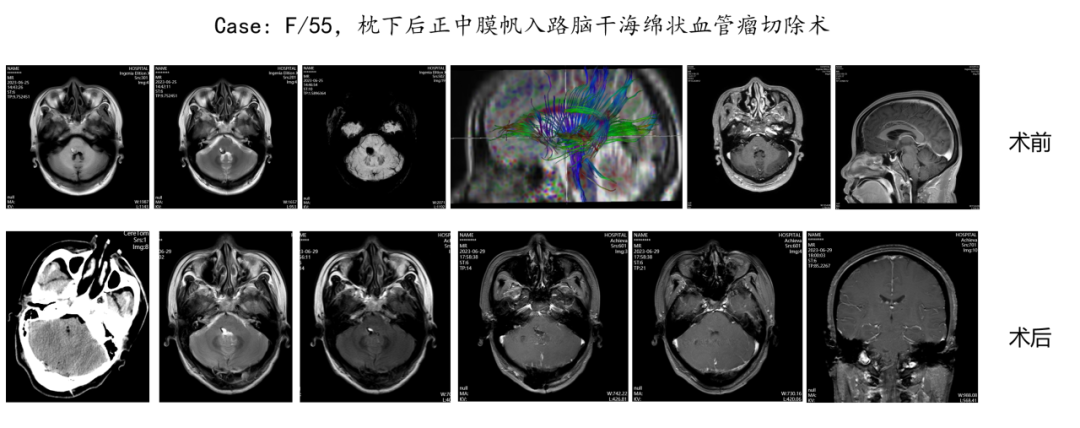

7

大脑深部肿瘤由于其位置深在,周围结构复杂,给手术治疗带来了极大的挑战。脑干是生命中枢所在地,脑干肿瘤手术风险极高。大脑深部肿瘤及脑干肿瘤的显微外科手术治疗是一项复杂而精细的技术,我们通过高超的手术技巧、丰富的临床经验及一流的硬件设备,为这类患者带来个体化的精准治疗,从而达到最佳的治疗效果。